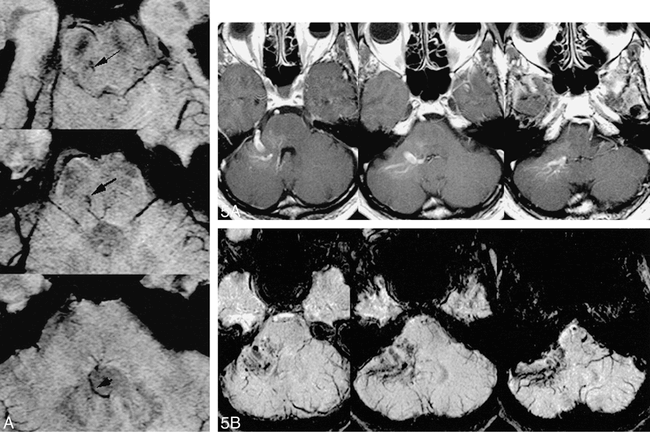

fig 5. Comparison of HRBV and contrast-enhanced T1-weighted images.

A, Contract-enhanced T1-weighted image (750/20 with one acquisition) shows enhancement of a typical venous angioma in the right cerebellopontine angle.

B, HRBV image shows numerous small vessels in addition to the enhancing vessels seen on the contrast study. These small vessels may represent small venous malformations or telangiectasias.